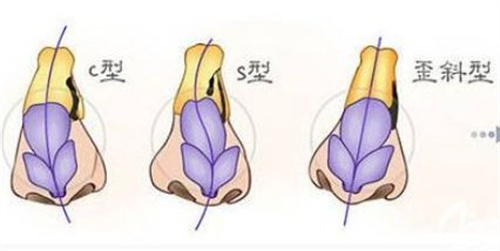

sweetsmile人工骨修复多少钱一次?12800-16800元起!M型/L型差价4000元,鼻基底填充12800元起,下巴塑形16800元起

sweetsmile人工骨修复多少钱一次?12800-16800元起!M型/L型差价4000元,鼻基底填充12800元起,下巴塑形16800元起想通过人工骨修复实现面部轮廓升级,却对价格体系一头雾水?当前主流的sweetsmile人工骨修复项目,单次费用在12800元至16800元区间浮动,其中M型与L型产品存在4000元差价,鼻基底填充项目起价1